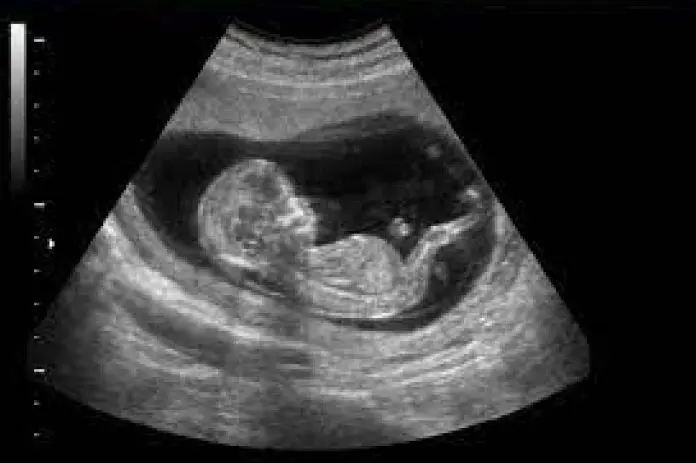

NT PLUS - Translucencia nucal

Este estudio prenatal es el marcador más importante en el primer trimestre para predecir el riesgo de presentar síndrome de Down u otras anomalías cromosómicas, así como problemas cardíacos congénitos importantes

• Scan fetal (Ecoanatomía Fetal / Scan Morfológico Fetal / Scan Detallado)

• Translucencia nucal / hueso nasal / doppler color ductos venoso (Fetaltest)